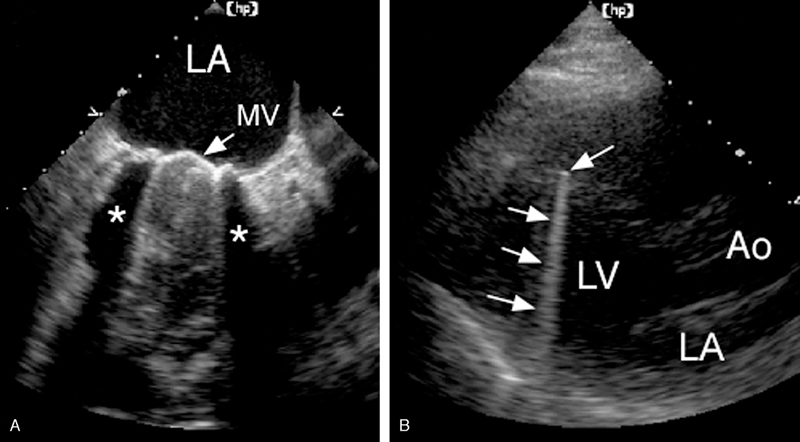

فحوصات تشخيصية لبعض امراض القلب والشرايين التاجية